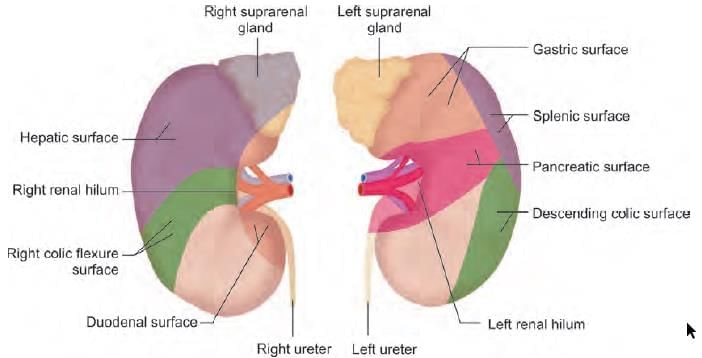

Anterior relations of third part of duodenum are all, except: (INI-CET May 2023)

A 25-year-old male presents to emergency with left upper quadrant pain, upon examination spleen was measured to 20 cm and further extending to the mid umbilicus. The extension of the spleen to left lower quadrant was prevented by: (NEET-PG 2021)